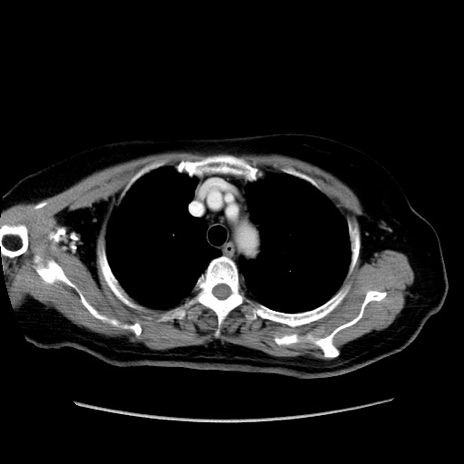

症例19(横断像)

【症例】80歳代女性

【主訴】下腹部痛

【現病歴】約8時間前より下腹部痛の出現あり、救急外来受診。

【既往歴】両側付属器切除

【身体所見】意識清明、下腹部正中に手術痕あり、その部位に一致して圧痛と反跳痛あり。腸蠕動音は亢進。

【データ】WBC 9300、CRP 0.15